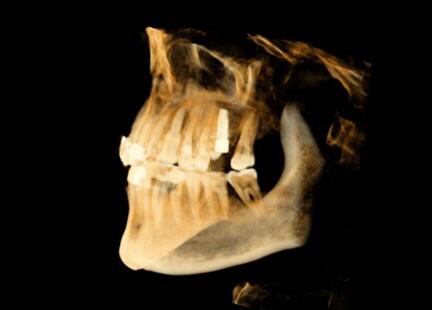

該系統(tǒng)用于口腔種植手術(shù)的術(shù)前計(jì)劃和術(shù)中引導(dǎo),通過對三維醫(yī)學(xué)影像的虛擬可視化應(yīng)用,采用專門的種植手術(shù)方案規(guī)劃軟件在三維模擬環(huán)境中進(jìn)行合理的種植方案設(shè)計(jì),結(jié)合精確的紅外光學(xué)定位技術(shù),實(shí)現(xiàn)手術(shù)器械、醫(yī)學(xué)影像和人體空間位置的融合。整個(gè)手術(shù)過程系統(tǒng)實(shí)時(shí)呈現(xiàn)病人解剖結(jié)構(gòu),全程監(jiān)控種植位點(diǎn)、角度、深度,從而實(shí)現(xiàn)精確種植。

運(yùn)用計(jì)算機(jī)三維重建與可視化技術(shù),清晰展現(xiàn)患者口內(nèi)解剖結(jié)構(gòu),保證了復(fù)雜病例的成功率。

導(dǎo)航病例1:上前牙缺失

患者信息:年輕,女性

主訴:上前牙殘根拔除術(shù)后六周,要求種植修復(fù)

現(xiàn)病史:患者因牙列不齊行正畸治療,約六周前正畸結(jié)束,并拔除上前牙殘根,要求種植修復(fù)。

檢查:21牙缺失,缺牙區(qū)牙齦狀況良好,無紅腫潰瘍,唇側(cè)牙槽骨豐滿度不足,近遠(yuǎn)中及齦頜距離可,原有過渡義齒佩戴良好。上下前牙淺覆頜覆蓋。全口衛(wèi)生良好。

種植體選擇:3.3*12mm士卓曼骨水平種植體